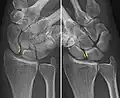

X-ray images indicate scapholunate ligament instability when the scapholunate distance is more than 3 mm, which is called scapholunate dissociation.[7] A static scapholunate instability is generally readily visible, but a dynamic scapholunate instability can only be seen radiographically in certain wrist positions or under certain loading conditions, such as when clenching the wrist, or loading the wrist in ulnar deviation.[6]

In order to diagnose a SLAC wrist you need a posterior anterior (PA) view X-ray, a lateral view X-ray and a fist view X-ray.[8] The fist X-ray is often made if there is no convincing Terry Thomas sign. A fist X-ray of a scapholunate ligament rupture will show a descending capitate bone. Making a fist will give pressure at the capitate, which will descend if there is a rupture in the scapholunate ligament.